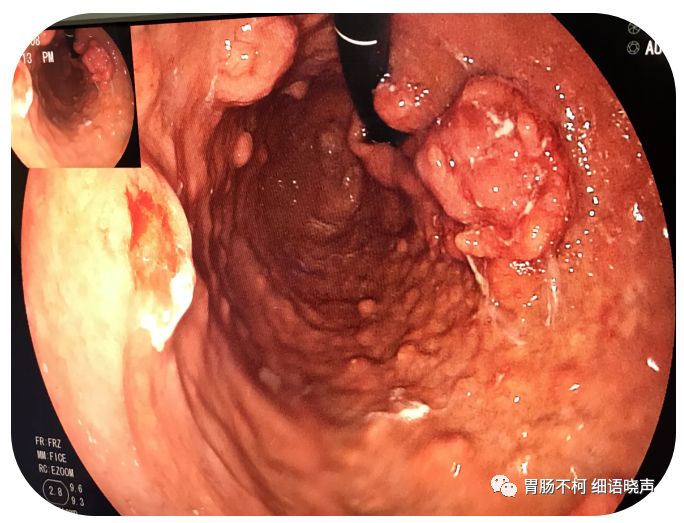

病例一:胃体大弯侧、小弯侧及前后壁见多发偏低回声、类圆形、膨胀感较强肿块

胃镜下可见大小不一的黏膜上皮下隆起样肿块

病理诊断:神经内分泌肿瘤,G1